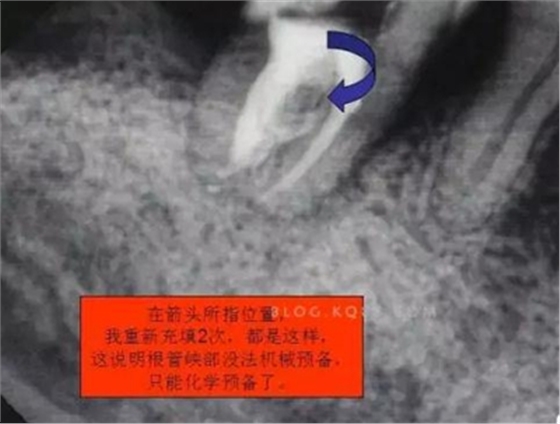

6.本病例,由于連接近遠中2個根管的融合區(qū)頰舌徑過于狹窄,在x線片上顯示不清,而唯一能表現(xiàn)的是近遠中分離的2個獨立的根管,將K銼放置到頰側(cè)根管內(nèi),有時在x線片上表現(xiàn)出根分叉處可能穿孔,這也是C型根管在x線上的重要特征。